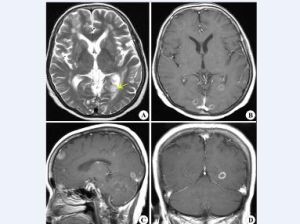

5.CT,MRI檢查,腦CT約半數顯示異常,炎性滲出物充填基底池及腦外側裂,部分患者腦實質內顯示結核瘤,直徑0.5~5cm,單發或多發,多位於額,顳及頂葉,增強掃描顯示環狀強化或密度增高。

腦MR採用Gd-DTPA增強,顯示基底池等部位強化,並較易發現腦實質內的結核瘤和小梗死灶。